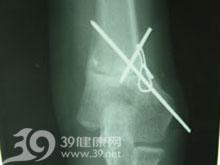

带8字包扎固定防治肱骨髁上骨折并发肘内翻-图

240x300 - 8KB - JPEG